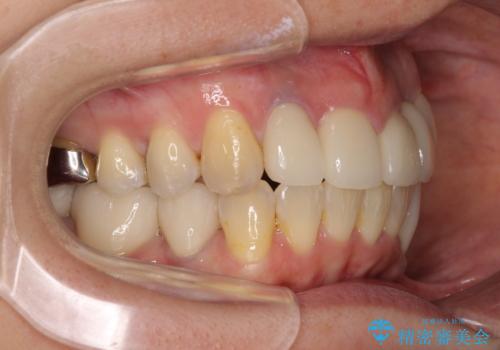

矯正治療によって前歯にスペースを作り、左右対称となるようにオールセラミッククラウンにて補綴治療を行うとしました。

他にも奥歯の咬み合わせに問題があったので、全顎的な矯正治療を行い、前歯以外にも口を開けたときに目立つ奥の銀歯をセラミッククラウンにて補綴治療を行うこととしました。

前歯の横幅が大きいことも気になっていたので、矯正治療で前歯5本の幅をコントロールしながら移動させ、治療開始前より一回りサイズの小さいセラミッククラウンを装着することができました。